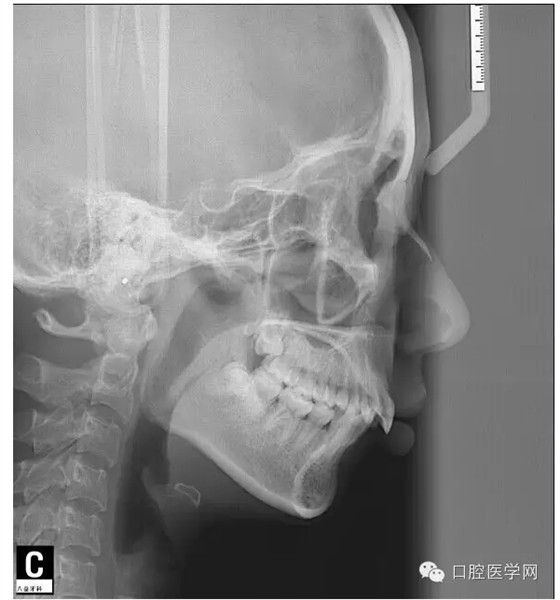

這是一位我同事接診的一位患者,成年女性,安氏II類,高角,下頜后縮,重度深覆合,上下中線右偏,原本做過一次矯正,4個4已經(jīng)拔除。

這個患者,II類高角,下頜后縮,所以我們不能抬高磨牙,另外兩個上頜中切牙牙根短小,也不能大幅壓入。